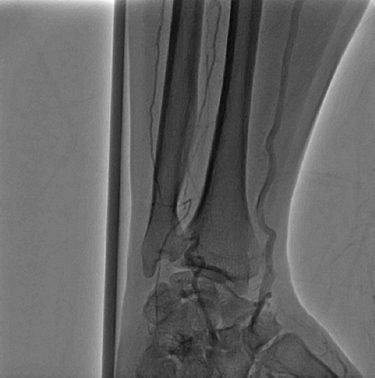

His presentation was consistent with acute limb ischemia, and emergent angiography revealed an occluded right brachial artery at the antecubital segment (Figure 1). Aspiration thrombectomy and mechanical rheolytic thrombectomy were attempted multiple times with slight improvement in blood flow. There was persistent large thrombus burden, and subsequent placement of fountain catheter and catheter directed thrombolysis were performed. Repeat angiography 12 hours after lytic infusion showed return of flow within the brachial artery but persistent occlusion in the ulnar artery (Figure 2). Multiple attempts of angioplasty were performed at the level of the bifurcation of the ulnar and radial arteries; the ulnar artery occlusion persisted. Angiography did show appropriate flow in the radial artery, an intact palmar arch, and retrograde filling of the ulnar artery (Figure 3). At this time the procedure was terminated, and the patient was sent to the CICU for observation.

Figure 3

Figure 3. Angiography shows a patent radial artery with reconstituted flow to an occluded ulnar artery by the palmar arch.